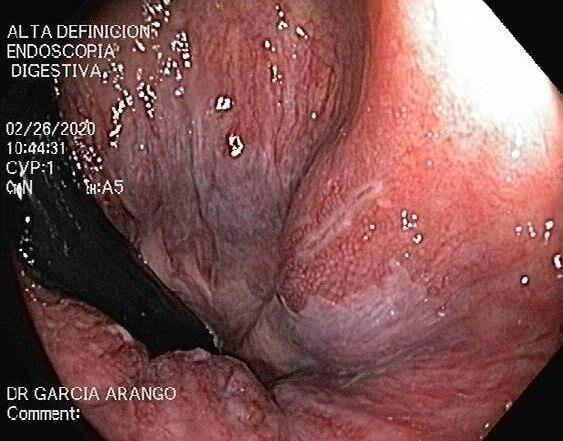

ENDOSCOPIA DIAGNÓSTICA Y TERAPÉUTICA AVANZADA CON ALTA DEFINICIÓN

⚕ Endoscopia de alta definición

⚕ Videoendoscopia y biopsias

⚕ Videocolonoscopia